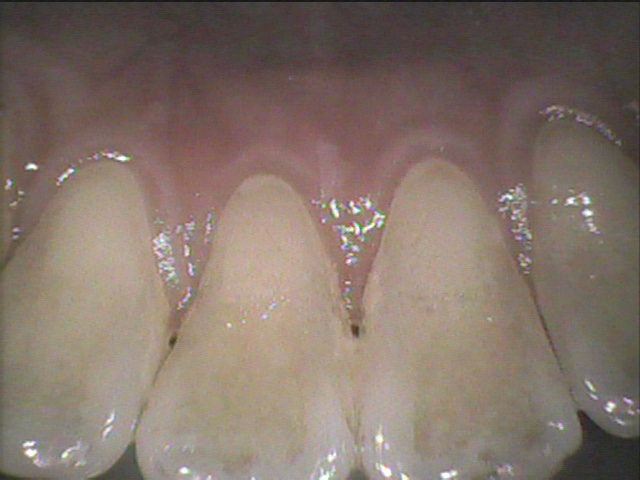

◎クリーニング前

⇩

◎クリーニング後

歯と歯の間や、歯と歯茎の境目の歯石を除去し綺麗になりました!✨